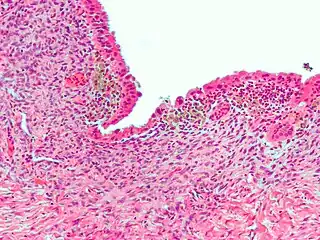

![]() Micrografía que muestra endometriosis (tinción H&E), una causa común de dolor pélvico crónico en las mujeres. | ||

- Endometriosis — el dolor causado por tejido uterino que se encuentra fuera del útero. La endometriosis se puede confirmar visualmente mediante laparoscopia en aproximadamente el 75% de las adolescentes con dolor pélvico crónico que es resistente al tratamiento, y en aproximadamente el 50% de las adolescentes con dolor pélvico crónico que no es necesariamente resistente al tratamiento.[3]